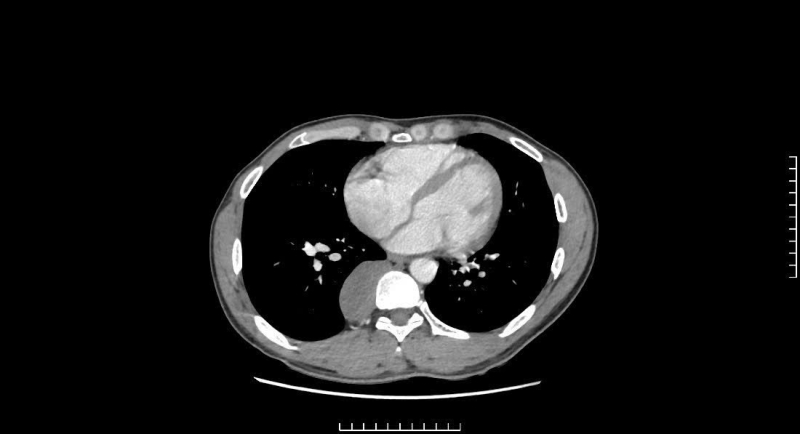

Bệnh nhân Thân V Q (38 tuổi, ở xã Tây Yên Tử, tỉnh Bắc Ninh) xuất hiện tình trạng khó thở, mệt mỏi, hụt hơi, khó nói, tê tay phải kèm các cơn giật mình vùng thân khi ngủ trong vài tháng nay. Gần đây, triệu chứng đau ngực tăng, thi thoảng giật mình thức giấc nên bệnh nhân đã đến Bệnh viện Bãi Cháy thăm khám. Người bệnh được thăm khám lâm sàng và thực hiện các xét nghiệm thăm dò chuyên sâu. Kết quả chụp CTscanner và MRI lồng ngực phát hiện khối u kích thước lớn 33x90x32mm nằm sát cột sống D7-D11. Các bác sĩ đã hội chẩn và chẩn đoán bệnh lý u trung thất sau, theo dõi u thần kinh.

Phim chụp khối u trung thất sau của người bệnh

Nhận định vị trí u nằm sâu trong lồng ngực – nơi tiếp giáp nhiều cấu trúc quan trọng như hệ tĩnh mạch đơn, cột sống, xương sườn, nhu mô phổi, bó mạch thần kinh liên sườn, ống ngực, thực quản, nguy cơ chèn ép thần kinh; Khi u phát triển quá lớn gây xẹp phổi, tắc mạch, suy hô hấp…. Ekip phẫu thuật của BSCKII Nguyễn Mạnh Hùng – Trưởng Khoa Thần kinh – Lồng ngực, Bệnh viện Bãi Cháy đã tiến hành phẫu thuật nội soi lồng ngực điều trị cho bệnh nhân. Dưới sự hỗ trợ của các thiết bị phẫu thuật nội soi hiện đại, phẫu thuật viên đã tiếp cận được khối u kích thước khoảng 5x10cm, mật độ chắc kéo dài từ cột sống D7-D11. Sau 3 tiếng, ca phẫu thuật diễn ra an toàn, thành công cắt bỏ triệt để u trung thất sau, phổi nở tốt, không rò khí và không chảy dịch bạch huyết. 5 ngày sau phẫu thuật, bệnh nhân phục hồi sức khỏe tốt.